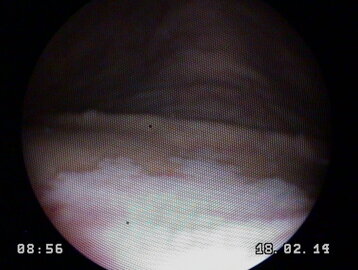

una carrellata di immagini per dare l'idea di cosa è possibile vedere con questo esame

Riduce il flusso urinario e provoca infiammazione